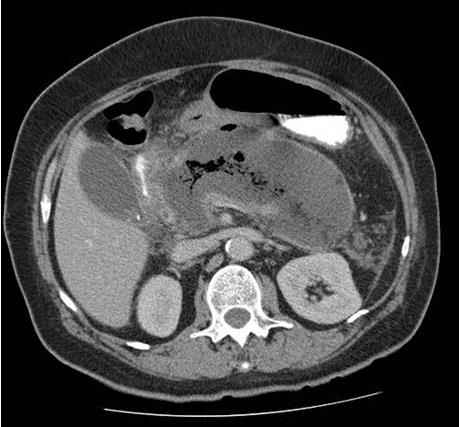

Homem, 48 anos, no nono dia de internação em UTI por quadro de pancreatite aguda necrotizante. No segundo dia, após controle de dor, passou a receber dieta por sonda nasoenteral de forma progressiva e com boa aceitação até o sétimo dia, quando teve recorrência de dor e vômitos, além de três episódios febris em 24 horas e taquicardia sustentada. Atualmente recebendo dieta 1 kcal/mL com volume diário de 1000 mL há dois dias e cinco episódios de vômitos nas últimas 12 horas. Paciente encaminhado hoje para realização de tomografia de abdome com o achado da Figura 11.

Figura 11. Tomografia computadorizada sem contraste de abdome

Tendo em vista a clínica e imagem apresentadas, assinale a alternativa que apresenta qual a hipótese diagnóstica e conduta mais adequada.